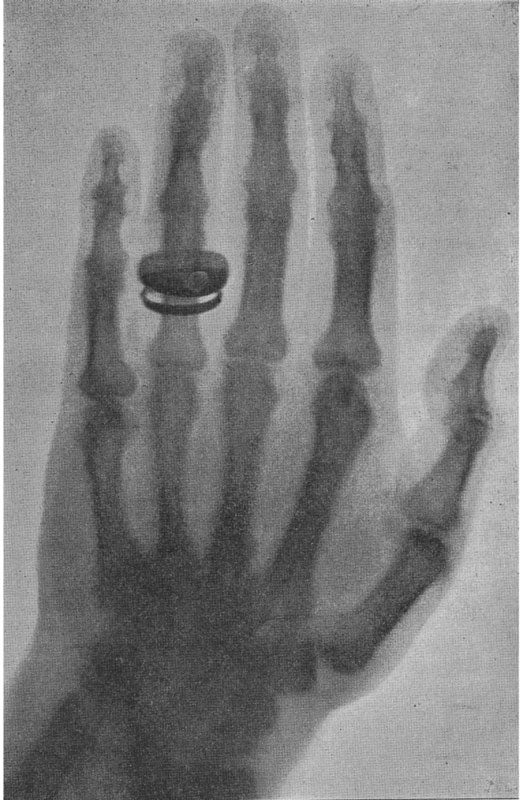

Image source: Röntgen, Wilhelm Conrad. “Ueber eine neue Art von Strahlen.” Sitzungsberichte der Wurzburger Physikalisch-Medicinischen Gesellschaft. No. 1, Würzberg, 1895, pp. 13.

Wilhelm Röntgen, a physics professor at the University of Würzburg, published his discovery of x-rays in the Sitzungsberichte der Wurzburger Physikalisch-Medicinischen Gesellschaft, the Meeting Reports of the Wurzburg Physical-Medical Society. Röntgen named the rays “X” to indicate the unknown nature of the radiation. In 1901 Röntgen received the first Nobel Prize in physics for his discovery.